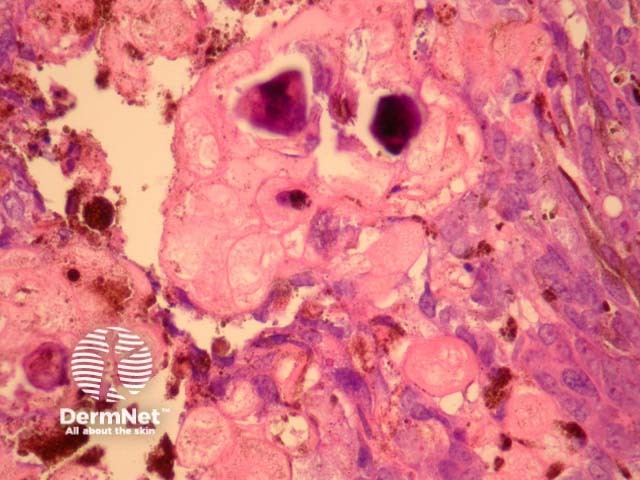

Sections through melanocytic matricoma show a well-circumscribed dermal tumour which may encroach and erode the overlying epidermis (figure 1). There is heavy melanin deposition. The tumour is made up of basaloid cells with some nuclear pleomorphism and conspicuous mitotic activity. Intermixed with these epithelial cells are a population of dendritic melanocytes (figures 1-4). There is focal “ghost cell” keratinisation (figures 5, 6).

Figure 3